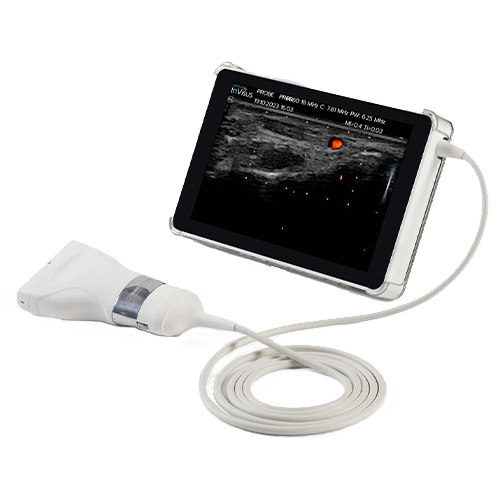

Il nuovo ecografo neuromuscolare InVisus Pro è progettato per consentire al team di identificare facilmente le strutture e punti di riferimento, aumentando la produttività e l’accuratezza, con uno schermo LED da 7″ che visualizza immagini full HD. Ottimizzato per le differenze di contrasto e struttura, InVisus Pro offre al personale medico un chiaro vantaggio in termini di sicurezza diagnostica.

L’ecografo neuromuscolare InVisus Pro è un tablet compatto che consente di visualizzare informazioni clinicamente utili per supportare il sistema EMG, direttamente nel punto di interesse. Visualizza i nervi e i muscoli, identifica rapidamente le neuropatie e le miopatie, o addirittura guida il posizionamento degli aghi.

Progettato per la portabilità e la flessibilità, InVisus Pro offre un’ampia gamma di opzioni di sonde per soddisfare le esigenze cliniche, indipendentemente dal suo utilizzo.

Progettato per la portabilità e la flessibilità

Come passo verso il futuro dell’ecografia neuromuscolare integrata di Natus, InVisus Pro è stato progettato per integrare qualsiasi sistema EMG, compresi i sistemi Nicolet EDX, UltraPro, Keypoint G4 e Keypoint Focus. Questa soluzione compatta e portatile è stata progettata appositamente per fornire un supporto in tempo reale al personale medico, proprio nel punto di assistenza. InVisus Pro offre anche la flessibilità di regolare facilmente le impostazioni e produrre immagini complete di misurazioni e annotazioni da aggiungere ai referti EMG.